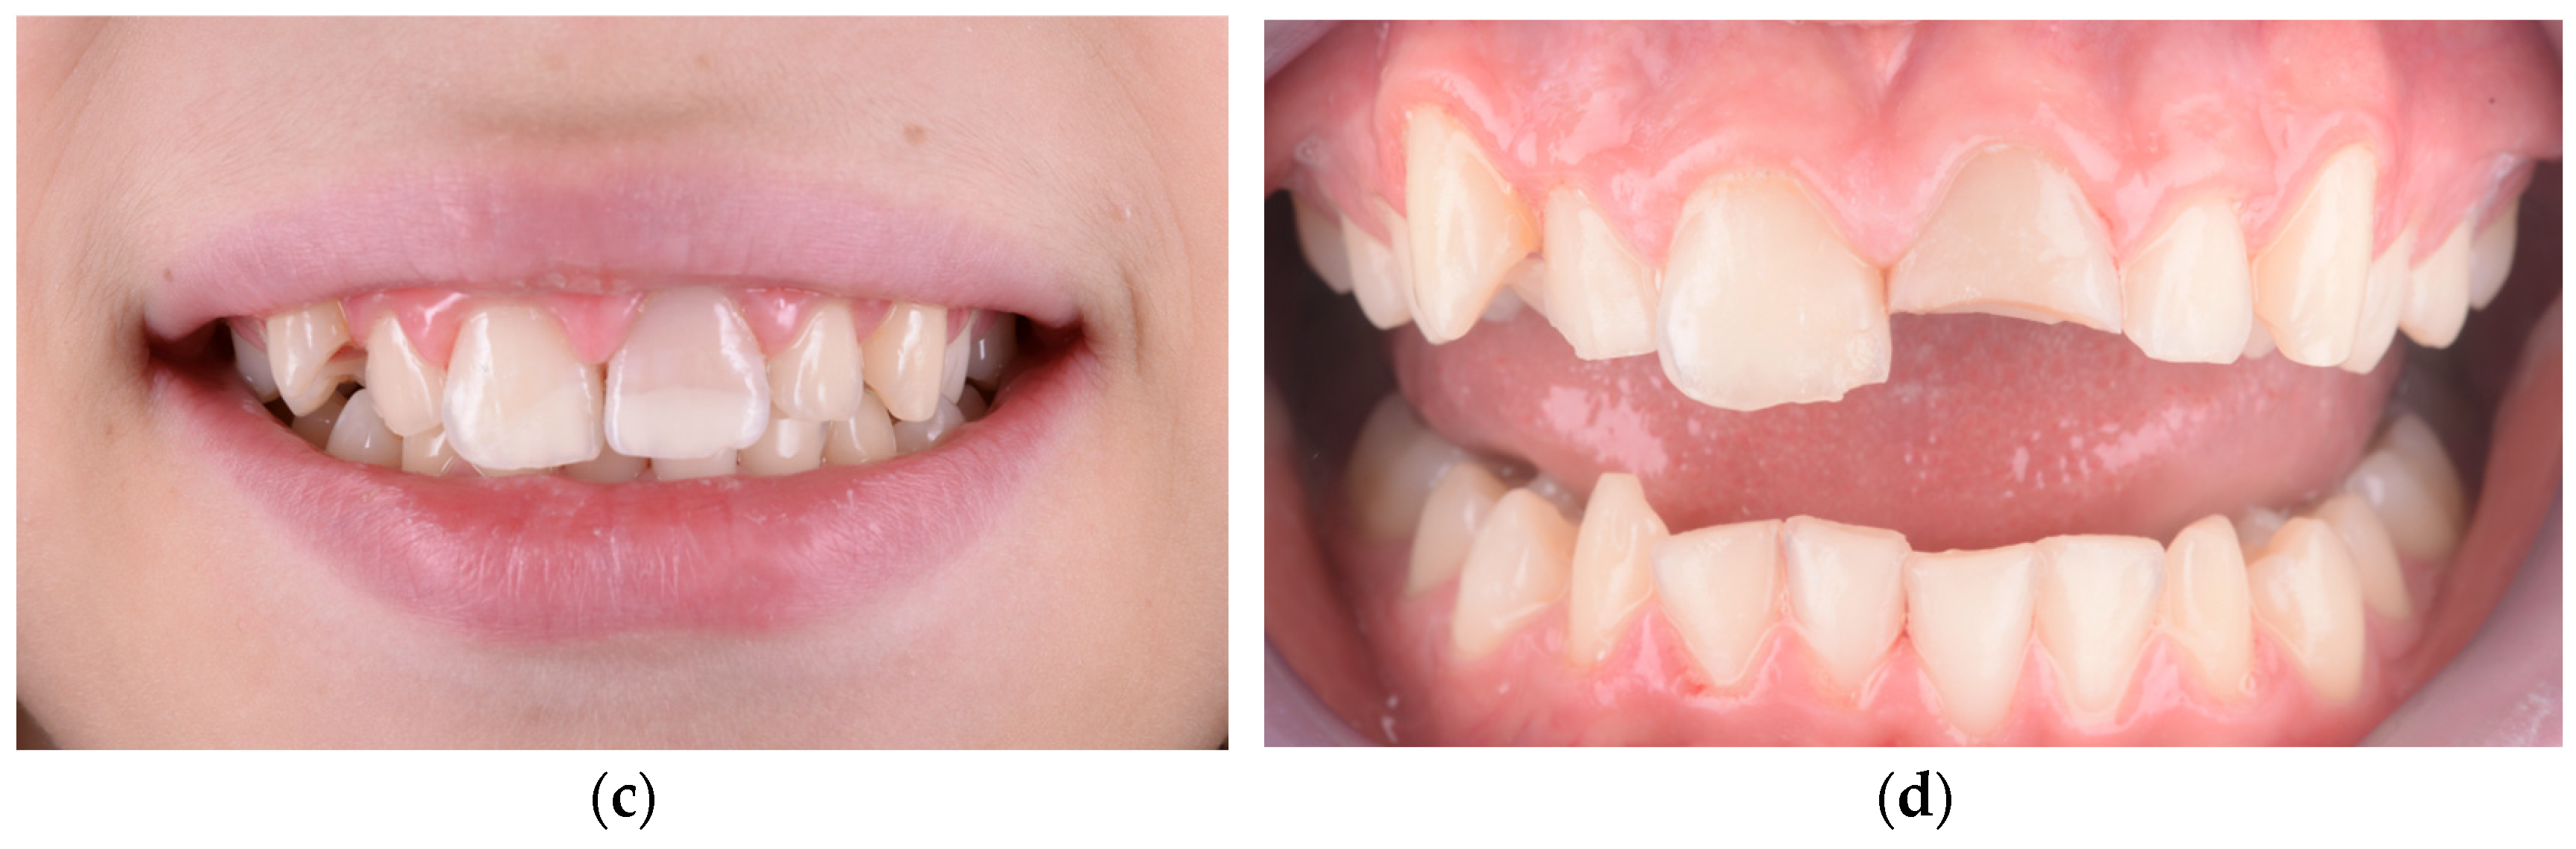

In the initial cases of this study, we employed fragment reattachment, a conservative technique frequently used in pediatric dental trauma [53,54,55]. However, our clinical outcomes indicated poor long-term stability and noticeable color discrepancies between the tooth and the reattached fragment, prompting us to discontinue this technique for the remainder of the study. The procedural steps and limitations of one such case are illustrated in Figure 4 and Figure 5. After the detachment or fracture of the reattached fragments, the affected teeth were subsequently restored using lithium disilicate crowns, which demonstrated superior esthetic and mechanical performance throughout the observation period.

Figure 4.

(a) Initial presentation showing crown fractures affecting both maxillary central incisors. (b) The two detached fragments retrieved intact, with well-defined fracture lines allowing for possible reattachment. (c) Immediate clinical appearance following fragment reattachment, showing acceptable alignment, although a noticeable color mismatch remains between the tooth structure and the reattached fragments. (d) Failure of both reattached fragments over time, with visible debonding and incisal-edge fractures under functional load.